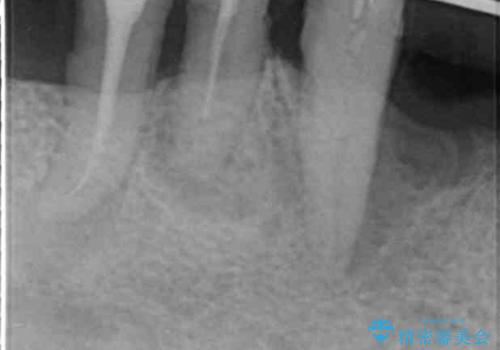

歯周組織検査・X線写真検査の結果、重度歯周病であることがわかりました。

残すことのできない歯を抜去し、入れ歯になることを回避すべくブリッジ治療を行いますが支台となる歯の歯周病を改善すべく歯周病により溶けた歯槽骨の再生治療を計画します。

再生治療により良好な歯槽骨の再生が得られ、入れ歯ではなく取り外しの必要のないブリッジによる機能回復を行うことができました。